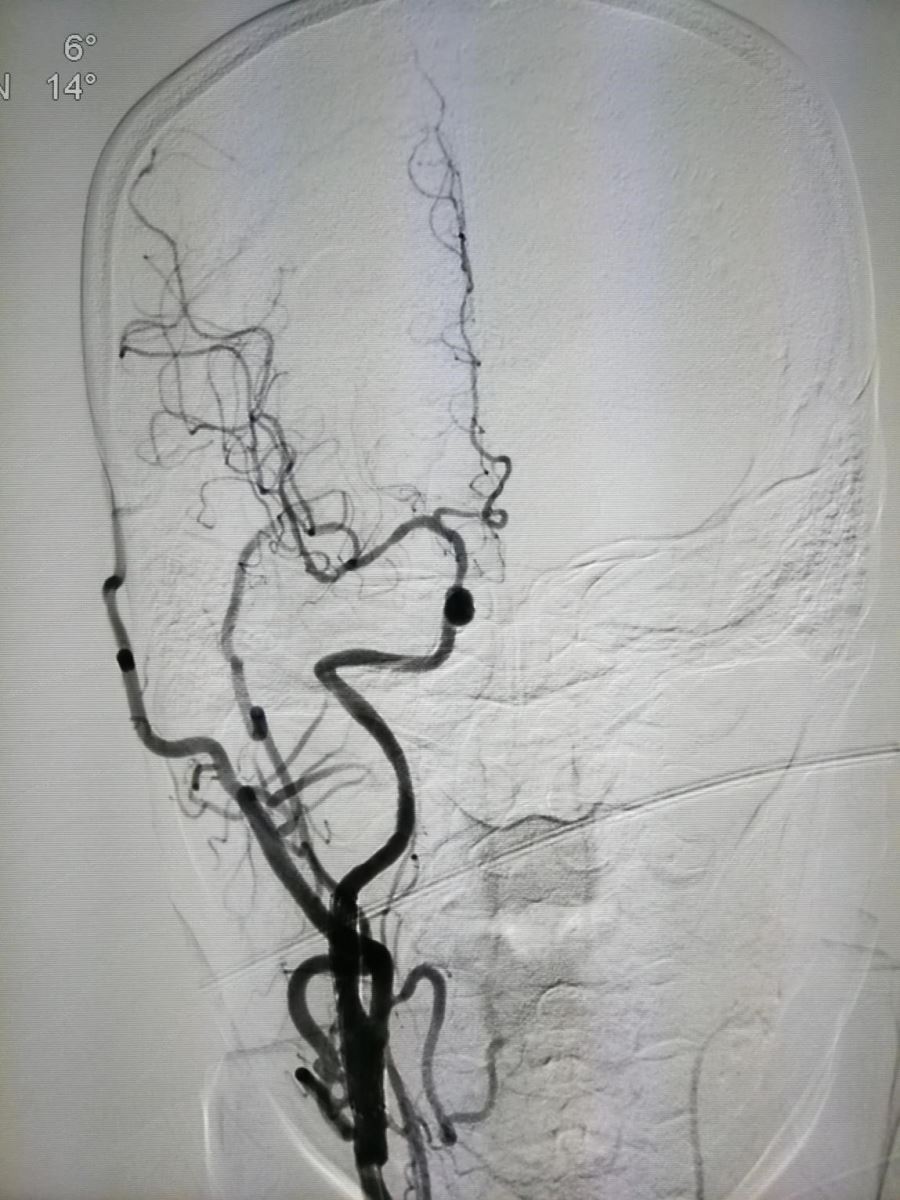

图6为术前斜位,图7为术后斜位。

.jpg)

图6 图7